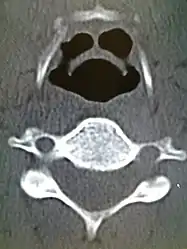

CT imaging showing the "halloween sign"

CT imaging, is rarely needed and can have a negative effect via respiratory distress.[13]